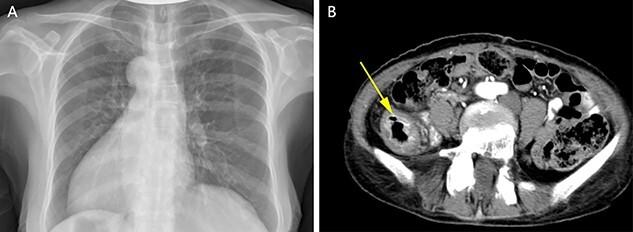

Situs inversus totalis (SIT) is a congenital disorder of anatomical position, and the operation of patients with total visceral inversion often brings great challenges to surgeons. Although there have been previously documented on patients with SIT and colonic cancer, this is the first case report of descending colon cancer in patient with SIT. The current report presents a case of a 67-year-old female patient with descending colon cancer and SIT. After preoperative preparation and discussion, open left hemicolectomy was performed for the patient. The postoperative recovery of the patient was smooth; however, there was a mild lymphatic leakage in the patient, which was cured by conservative treatment for 5 days. The patient was discharged on postoperative Day 10. There was no tumor recurrence or other discomfort in 1 year follow-up period.

全内脏反位(SIT)是一种先天性解剖位置异常疾病,全内脏反位患者的手术常常给外科医生带来巨大挑战。尽管此前已有关于SIT患者合并结肠癌的文献记载,但这是首例全内脏反位患者降结肠癌的病例报告。本报告介绍了一例67岁患有降结肠癌和全内脏反位的女性患者。经过术前准备和讨论,为该患者实施了左半结肠切除术。患者术后恢复顺利;然而,患者出现轻度淋巴漏,经5天保守治疗治愈。患者于术后第10天出院。在1年的随访期内无肿瘤复发或其他不适。